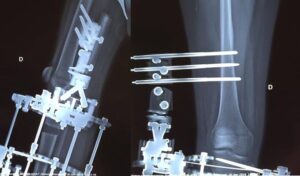

Based on the expected length discrepancy, the number of procedures necessary to equalize the length difference at the end of growth will be determined.

When establishing a treatment plan for leg hypoplasia , it should be considered that in general:

- Each lengthening intervention can achieve a lengthening of the segment of up to 7/8 cm (maximum 5 cm in children under 4 years old)

- procedures must be separated from each other by at least 4 years

- The possible presence of shortening of the femur must also be considered in the therapeutic program (see related sheet).